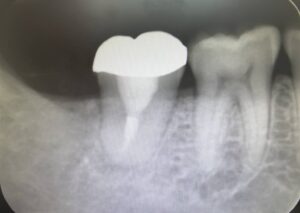

根管治療後は経過を観て問題ないことを確認してから最終的に補綴を被せています🦷

↑こちらの写真は根管治療後、根の先までしっかり薬が入り、土台と被せ物まで装着した最終状態です。